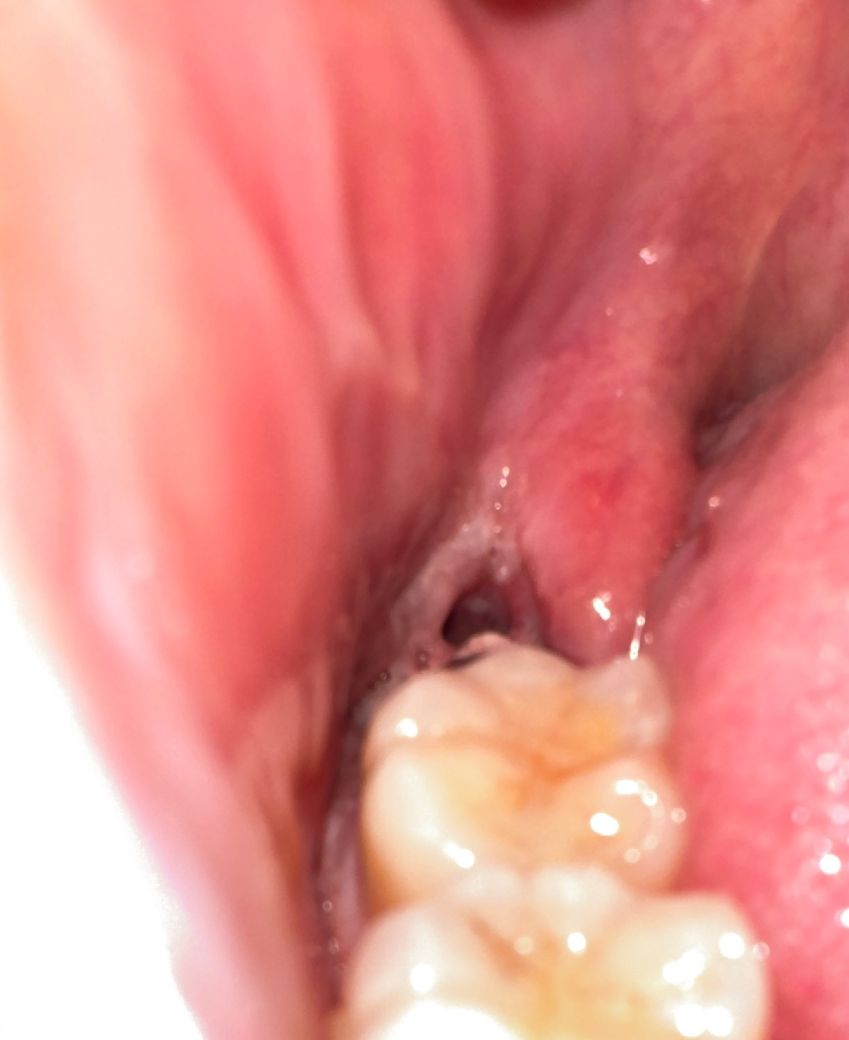

사랑니 발치 후에 혈병이 없는것같아요

사랑니를 뽑고 3일차인데 혈병(피딱지)가 없는것같아요 술 담배 안했고 2일차에 죽 한끼 먹었어요

사진상으로는 잘 안보이겠지만 앞쪽엔 혈병 비슷한게 흰색으로 변해있습니다 뒤쪽에는 뿌리부분이 뻥 뚫려있구요 ㅠ

1. 혈병(피떡)은 원래 발치 후 1~2일차에 흡수되어 잇몸과 잇몸뼈 재생에 필요한 세포로 바뀝니다

2. 빈 공간이 저렇게 보여지는게 정상입니다 이제 점차 잇몸과 잇몸뼈가 차오르고 이건 시간이 많이 걸립니다